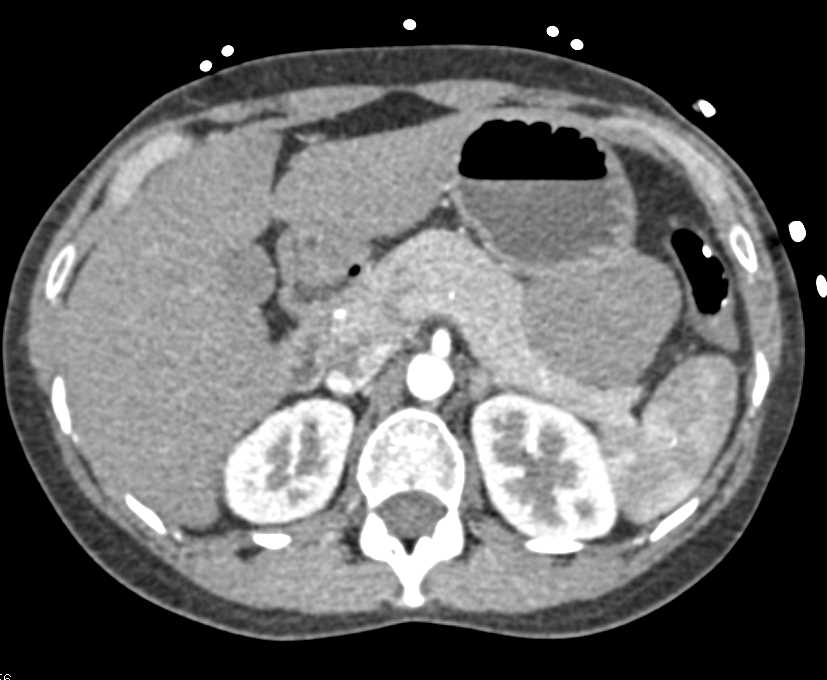

Mass Pushes on Tail of Pancreas was Ganglioneuroma